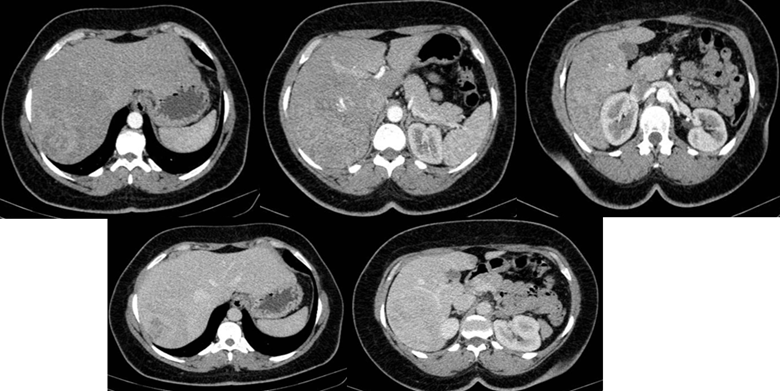

Paraclínica: La Tomografía de Abdomen y Pelvis con contraste intravenoso, trifásico destaca un hígado aumentado de tamaño de forma conservada. Se evidencia a nivel del lóbulo derecho, una voluminosa tumoración sólida, heterogénea, con áreas de realce con el contraste y áreas hipodensas centrales; midiendo 111 por 82mm. Concomitantemente presenta 2 imágenes quísticas periféricas. Sin dilatación de la vía biliar. (Figura 1).